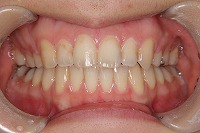

25歳6ヵ月

正面

上の前歯が出ている事を主訴に来院された、23歳2か月の女性です。診断「下顎骨の後方回転による骨格性上顎前突で開咬を伴う」上顎は両側第1小臼歯、下顎は抜歯をせず治療を行いました。